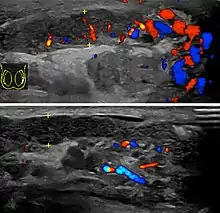

| Diagnostic method | Based on symptoms, ultrasound[1] |

In those who are young and sexually active, gonorrhea and chlamydia are frequently the underlying cause.[1] In older males and men who practice insertive anal sex, enteric bacteria are a common cause.[1] Diagnosis is typically based on symptoms.[1] Conditions that may result in similar symptoms include testicular torsion, inguinal hernia, and testicular cancer.[1] Ultrasound can be useful if the diagnosis is unclear.[1]

Diagnosis is typically based on symptoms.[1] Conditions that may result in similar symptoms include testicular torsion, inguinal hernia, and testicular cancer.[1] Ultrasound can be useful if the diagnosis is unclear.[1]

Epididymitis usually has a gradual onset. Typical findings are redness, warmth and swelling of the scrotum, with tenderness behind the testicle, away from the middle (this is the normal position of the epididymis relative to the testicle). The cremasteric reflex (elevation of the testicle in response to stroking the upper inner thigh) remains normal.[1] This is a useful sign to distinguish it from testicular torsion. If there is pain relieved by elevation of the testicle, this is called Prehn's sign, which is, however, non-specific and is not useful for diagnosis.[13] Before the advent of sophisticated medical imaging techniques, surgical exploration was the standard of care. Today, Doppler ultrasound is a common test: it can demonstrate areas of blood flow and can distinguish clearly between epididymitis and torsion. However, as torsion and other sources of testicular pain can often be determined by palpation alone, some studies have suggested that the only real benefit of an ultrasound is to assure the person that they do not have testicular cancer.[14]: p.237 Nuclear testicular blood flow testing is rarely used.